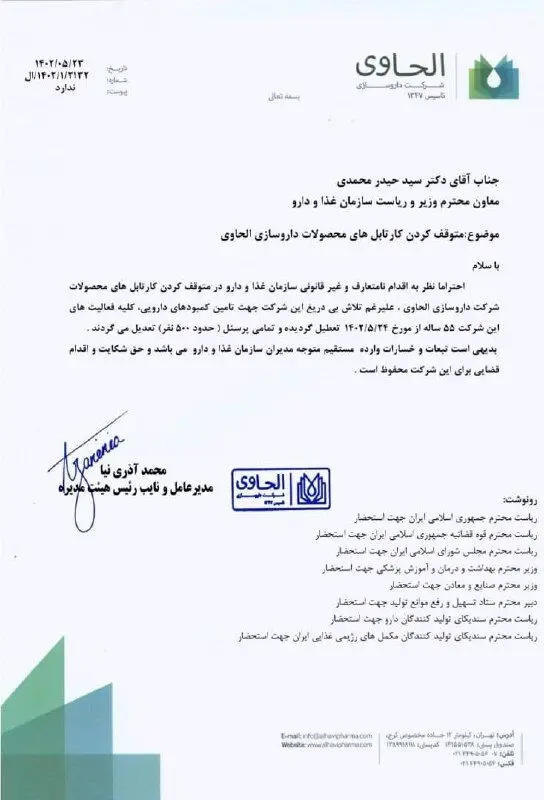

محمد آذری نیا مدیرعامل شرکت داروسازی الحاوی با ارسال نامهای به حیدر محمدی رئیس سازمان غذا و دارو ، اعلام کرد: در پی اقدام نامتعارف و غیر قانونی سازمان غذا و دارو در متوقف کردن کارتابل محصولات شرکت داروسازی الحاوی، علیرغم تلاش های این شرکت جهت تامین کمبودهای دارویی، کلیه فعالیت های این شرکت ۵۵ ساله از امروز ۲۴ مرداد تعطیل شده و تمام حدود۵۰۰ نیروی انسانی ، تعدیل می شوند.

بدیهی است تبعات و خسارات وارده مستقیم، متوجه مدیران سازمان غذا و دارو بود و حق شکایت اقدام قضایی برای این شرکت محفوظ است.

این نامه به روسای جمهور، قوه قضائیه و مجلس، دو وزیر صنعت و بهداشت و... رونوشت شده است.